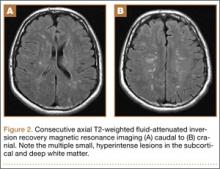

A previously healthy 50-year-old man presented to the emergency room in transfer from an outside hospital after a rollover motor vehicle collision in which he was ejected approximately 50 feet. Injuries included a right proximal humerus fracture/dislocation (Figure 1), right ulnar styloid fracture, L1 compression fracture, and multiple rib fractures. On admission, the patient had an ethanol level of 969 mg/L (.097%) and a urine drug screen positive only for opioids, presumably because of pain medication given that day. He denied a history of alcohol abuse and reported consuming 2 to 3 beers per week. The patient was awake, alert, and oriented with a Glasgow Coma Scale (GCS) of 15. He was tachycardic (heart rate, 126), tachypneic (respiratory rate, 24), and febrile (temperature, 38.6°C [101.5°F]), and his white blood cell count was elevated at 29.5×109/L. On examination, his right arm was found to be neurovascularly intact; it was placed in a sling with a forearm splint, and the patient was admitted to the intermediate special care unit on spine precautions with a plan for right shoulder hemiarthroplasty the following day.

Overnight the patient’s mental status began to deteriorate, and approximately 10 hours after initial assessment, he was not answering questions but was able to respond to some commands. On hospital day 2, approximately 20 hours after initial assessment, the patient had a GCS of 8, was not responding to commands, and moved only in response to painful stimuli. The patient had been prescribed morphine by patient-controlled analgesia and had received intravenous hydromorphone on the day of admission, although the amount of medication delivered was not thought adequate to explain this deterioration. On the morning of hospital day 2, noncontrast brain computed tomography (CT) was normal with no evidence of intracranial hemorrhage or infarct. This was followed by brain magnetic resonance imaging (MRI), with the T2-weighted images showing numerous, small hyperintense lesions in subcortical and periventricular white matter, corpus callosum, basal ganglia, brain stem, and cerebellar hemispheres (Figure 2). The lesions also showed hyperintensity on diffusion-weighted MRI and were interpreted to be consistent with multiple, tiny infarcts (Figure 3). In addition, susceptibility-weighted sequences showed low signal in the same areas, suggesting multiple microhemorrhages, a pattern consistent with FES. Oxygen saturations remained 95% to 99%, and chest radiograph revealed clear lung fields without infiltrate. On hospital day 2, the patient was transferred to the intensive care unit and intubated for airway protection owing to an inability to clear secretions, although arterial blood gas levels remained normal. An echocardiogram revealed no right-to-left shunt, such as a patent foramen ovale (PFO); an electroencephalogram showed no seizure-like activity. No petechial rash was noted on skin examination. The patient was treated with supportive care. Right shoulder hemiarthroplasty was performed on hospital day 7 without complications (Figure 1). On hospital day 13, the patient was following commands and on day 14 he was extubated. His mental status continued to improve, and he was discharged to a rehabilitation facility after 36 days. On last follow-up, 6 months after initial injury, the patient was recovering well with no residual neurologic deficits and only minor limitation in range of motion of the right shoulder.